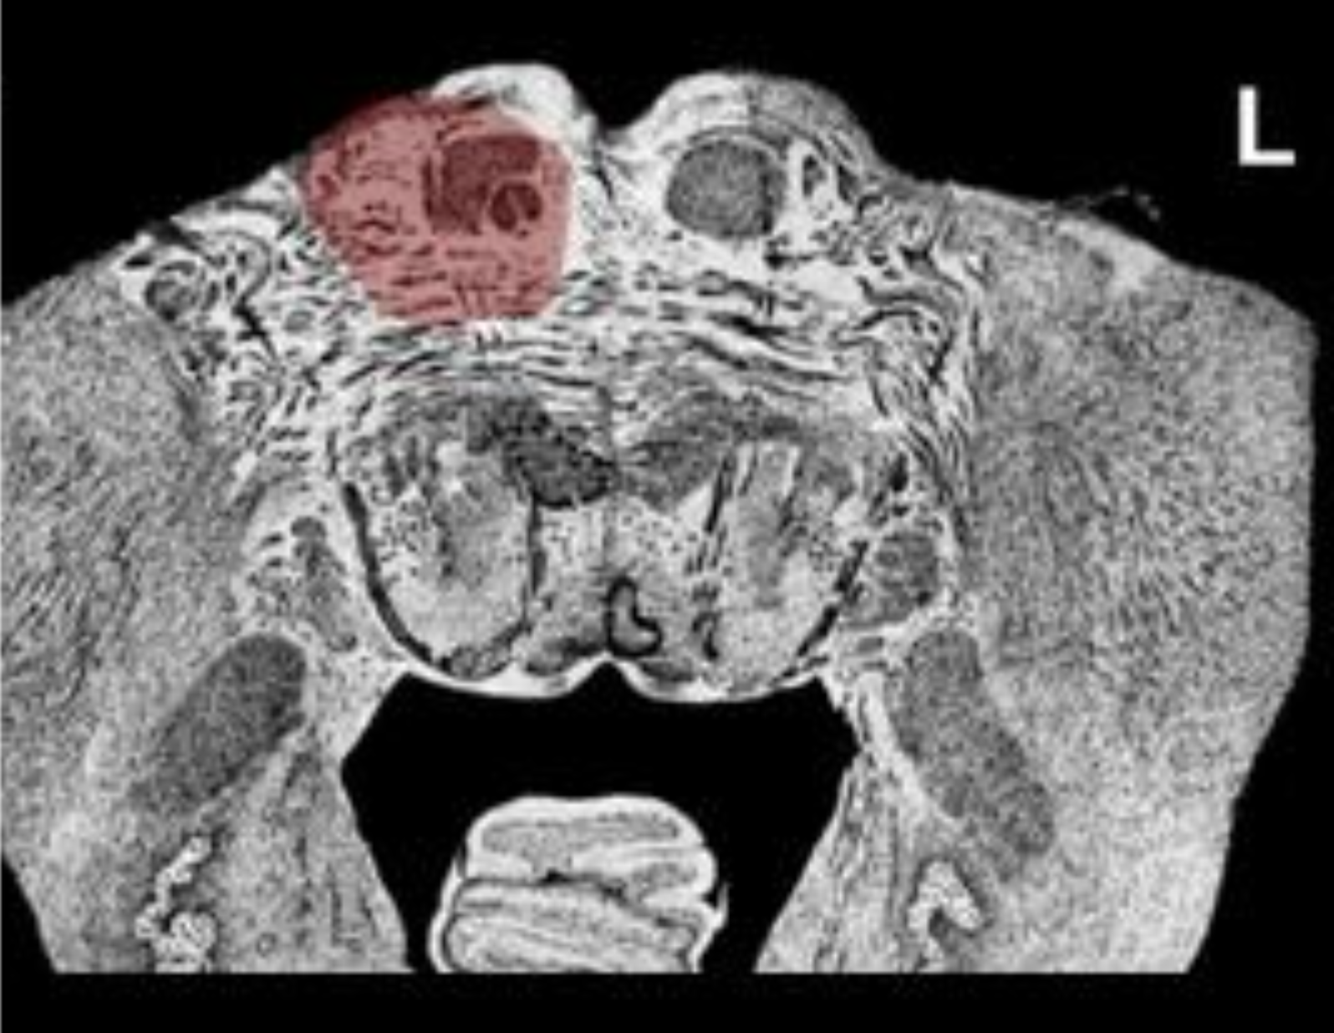

What is the name/location/results of the condition caused by a lesion in the shaded area?

Medulla, mid olive.

Right alternating hypoglossal hemiplegia

1) Destruction of the hypoglossal nerve results in ipsilateral paralysis of the muscles of the tongue, and atrophy of the ipsilateral muscles of the tongue

2) Destruction of the corticospinal tract at this level results in contralateral spastic hemiplegia